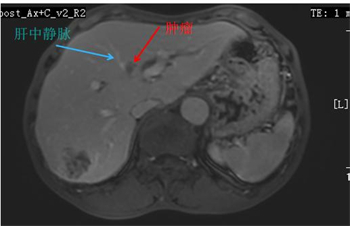

经过仔细分析肝内病灶的数目及特点发现,肝内共有8个病灶,6个病灶位于肝脏右后叶(S6、S7),可做标准肝右后叶切除术,1个病灶位于肝左内叶(S4)表面,可做局部切除,1个病灶位置极为特殊,位于肝左内叶(S4)深部,肿瘤形态不规则且紧邻肝中静脉起始部位,毗邻第一肝门,该位置的肿瘤是无法切除的,只能术中消融或术后放疗,但放疗的效果不及术中消融的效果,术后易复发。对于紧邻血管和第一肝门的的肿瘤进行消融是极其困难的,无论是布针的路径和能量的设置都具体很大的挑战。

S4拟行消融的病灶